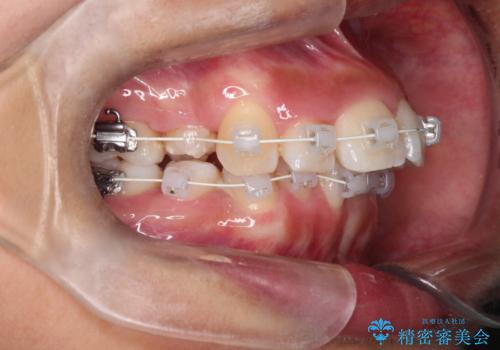

- 矯正装置

- 審美装置

- 前歯の凸凹を主訴に来院されました。

抜歯を行い、ワイヤー矯正にて治療を行いました。

CTにて骨を確認し、側切歯の歯根をこれ以上頬側に出せないことを確認しています。